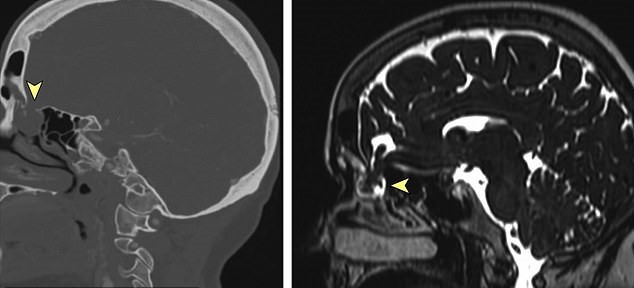

Her doctors took CT scans and photographs of her skull and nasopharyngeal passageway, and that’s when they discovered a hole at the base of her skull.

According to a 2017 scan, the defect was already there and the cerebrospinal fluid started sipping after the swab prodded the pre-existing problem.